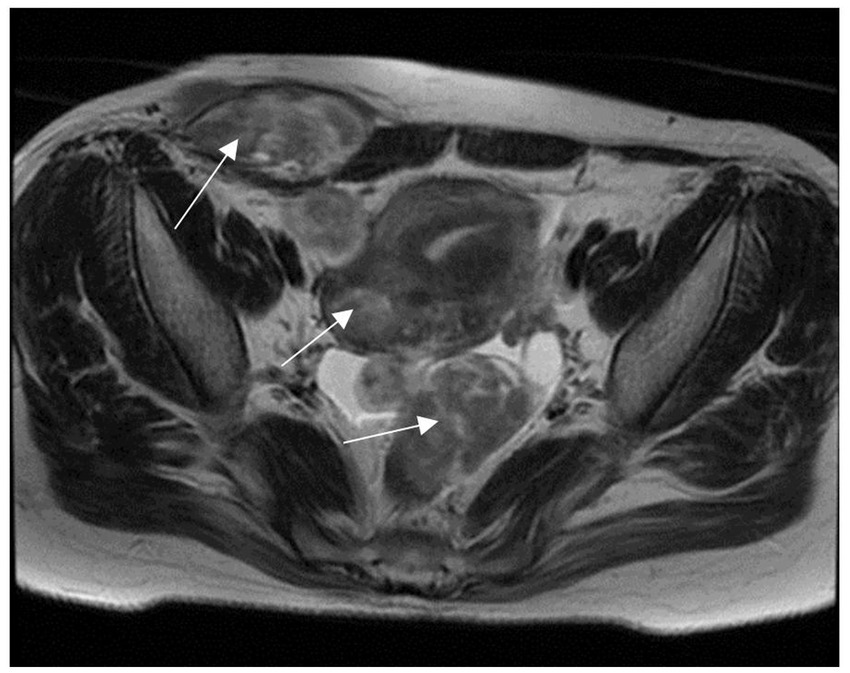

Ultrasonography revealed a uterus measuring 6.1 × 7.0 × 5.0 cm, exhibiting multiple fibroids and adenomyosis, with the largest fibroid, measuring 4.7 × 3.7 cm, located in the posterior uterine wall. The right lower abdominal wall revealed multiple hypoechoic regions beneath the skin. Some of these regions were in close proximity to the uterus, with the largest measuring 7.7 × 7.3 × 2.8 cm. Abdominopelvic magnetic resonance imaging (MRI) showed multiple masses in the anterior abdomen, myometrium, and lower pelvic cavity, ranging from 2.0 to 6.8 cm in length (Figure 1). A complete blood test revealed a hemoglobin level of 11.8 g/dL and a serum CA125 level of 36.3 U/mL.

Figure 1

MRI shows the right anterior abdominal wall, myometrium, and multiple pelvic masses.